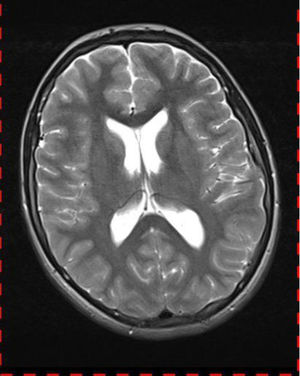

Abb. 3.3 T2 TSE transversal: keine intraventrikuläre Drucksteigerung, keine Zeichen einer Liquordiapedese

Bei dieser Untersuchung wurde übersehen, dass die Kleinhirntonsillen in das Foramen magnum disloziert waren und eine Arnold-Chiari-Malformation mit Erweiterung des 4. Ventrikels und des Aquäduktes inklusive Kleinhirntonsillentiefstand vorlag. Bei zwischenzeitlich auswärtig erfolgtem CT der HWS wurde eine Anlagestörung im kraniozervikalen Übergang beschrieben. Eine Kontrolluntersuchung des Kopfes weitere 4 Monate später dokumentierte neben einem medullären Ödem einen progredienten Tonsillentiefstand, der zur neurochirurgischen Behandlung mit operativer Erweiterung des Foramen magnum führte.